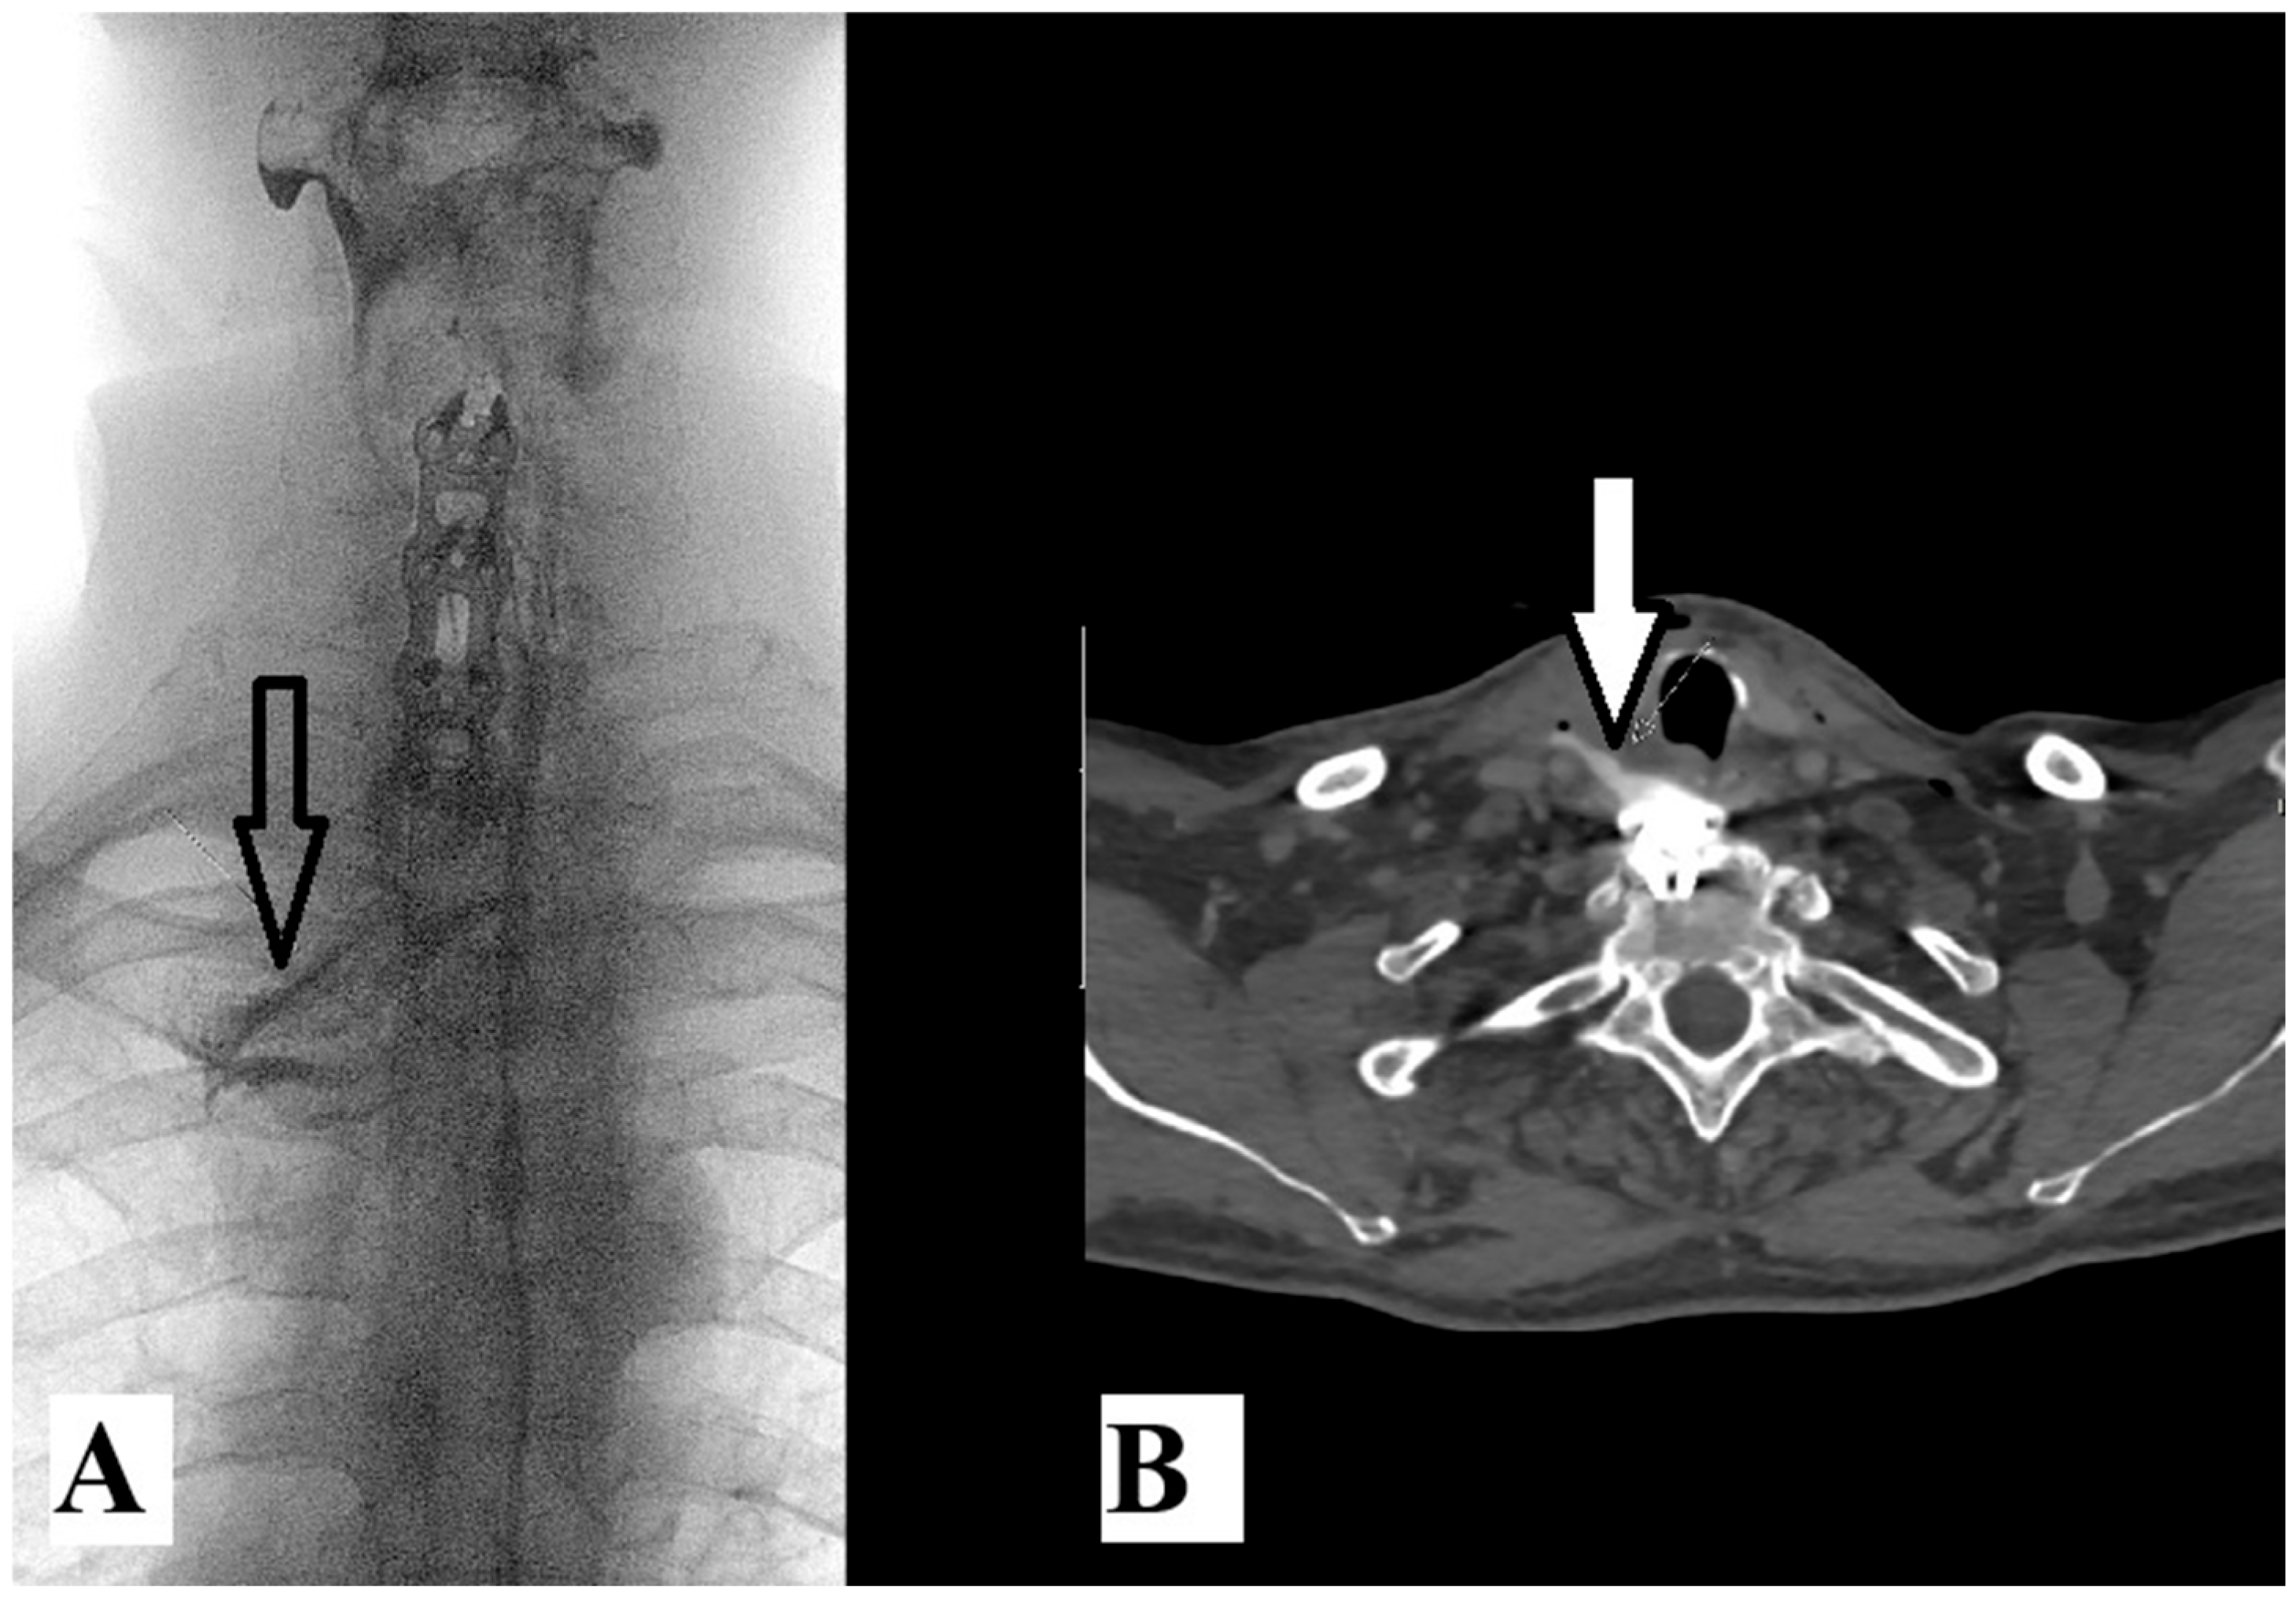

From another aspect, according to the same search engines and with the addition of the words “esophageal injury”, only three cases of AS with esophageal injury [8,9,10] emerged in the last ten years (Table 1). Injury of the esophagus is a rare but serious complication when cervical spine fracture occurs in patients with AS. There are two possible mechanisms of esophageal injury: direct or acute injury or delayed injury after hardware failure. Our patient had luxation fracture at the C6–C7 level (Figure 2A). He first underwent Crutchfield traction and anterior C5-T1 fixation with a titanium plate. Six months after surgery, the patient underwent re-surgery due to hardware failure and esophageal injury (Figure 2B). Further radiologic examination should be performed to confirm these devastating injuries (Figure 2B and Figure 3A).

Figure 3. Fluoroscopy image of contrast media swallow test (A) reveals extralumination (arrow) of water-soluble contrast media through the perforated upper esophagus. Axial CT image (B) at the level of the first thoracic vertebral body showing extralumination (arrow) of previously swallowed water-soluble contrast media into the prevertebral and carotid space of the neck.